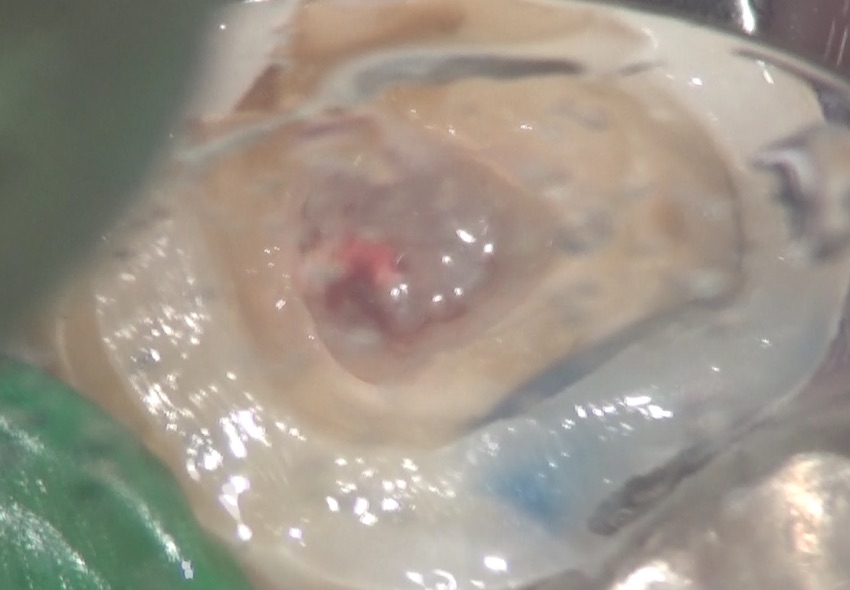

虫歯を取り除いています。

キレイに取り除くと、歯の内部から、出血をなにやら白い体液が一緒に出てきました。

触ると、ネチョネチョしています。

これは膿でした。この写真は、その膿と出血が混ざっているところです。